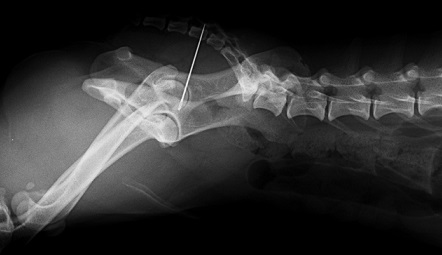

Hier links ziet u de naald ter hoogte van het midden van zijn bekken.

Op de 2e röntgenfoto, die genomen is vanuit zijigging, zien we dat het een flinke naald is die een eind omhoog steekt richting de staart. U gelooft het misschien niet, maar aan de buitenkant van Pico was niets te zien...